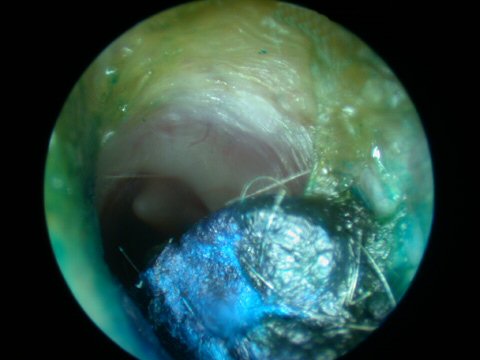

Fungal infection of the ear canal